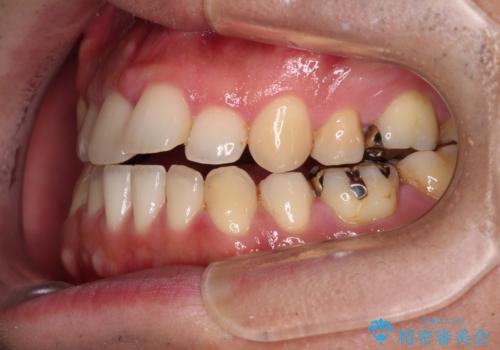

- 抜歯矯正の後戻りを気にして来院された患者様です。

舌の突出癖によるオープンバイトになり、前歯の叢生が後戻りしていました。

舌のトレーニングを行いながら、インビザラインを用いて矯正治療を行うこととしました。